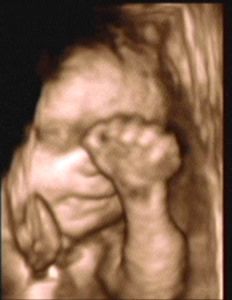

3D/4D SONOGRAPHY 18-24 WEEKS

- Normal Sonography is 2 dimensional. In 3 dimensional Sonography the information is obtained simultaneously in 3 planes (X, Y & Z).

- Highly sophisticated software reconstructs this information into a distinct 3D image.

- From a continuous 3D acquisition you get a live action view. It is known as 4D where 4th dimension is time.

- Improved identification of suspected or detected anomalies.

- More accurate identification of the extent & size of anomalies.